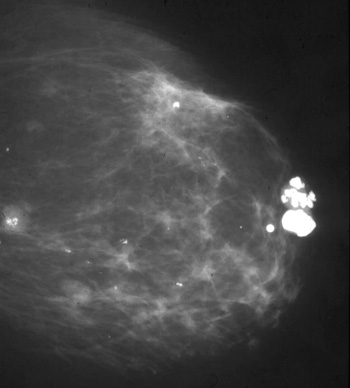

يمكن للعديد من حالات الثدي الحميدة أن تنتج كثافة متصاعدة قد لا يمكن تمييزها في التصوير الشعاعي للثدي عن السرطان.

تمت مصادفة كثافة الكتلة الموضحة في:

تندب ما بعد الخزعة

نخر الدهون المؤلم

خراج الثدي

التصلب الغدي…